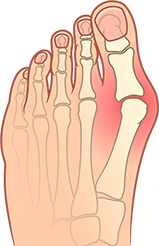

Maria 48 anni

L'osso sul piede è molto, molto doloroso e brutto, causa problemi quando si cammina, si scelgono le scarpe e mentre le si indossa. L'ho capito da un esempio personale. Con l'età, la dimensione della gamba è diventata più grande, apparvero i piedi piatti trasversali, I dottori dissero che solo la chirurgia avrebbe aiutato, ma ho una paura terribile della chirurgia, quindi ho deciso di utilizzare metodi meno invasivi, quindi mi sono imbatutta in Fortolex, problemi alle gambe come mai avvenuti.Ottimo prodotto!

Olivia, 50 anni

In generale, le articolazioni sono un punto debole nelle donne della nostra famiglia, e l'esacerbazione non si verifica nella vecchiaia, ma più vicino alla mezza età - a 30-40 anni. Per me, questo si è manifestato stesso sotto forma di alluce valgo. Fino a quando non ho usato Fortolex, ho pensato che questa fosse la mia croce per la vita e che potevi dimenticarti per sempre delle scarpe belle ed eleganti.Ma, come si è scoperto, questa cosa è facile da trattare.Con Fortolex, la protuberanza sul piede ha iniziato a diminuire di giorno in giorno, come per magia. Ora è quasi invisibile.

Amedeo, 65 anni

Onestamente, la protuberanza sulla gamba non mi ha dato molto fastidio. Beh, sì, fa male camminare, devo scegliere delle scarpe ortopediche. Ma sono abituato a sopportare i disagi nella mia vita, quindi non l'ho fatto non ci vedo niente di sbagliato in questo, soprattutto perché sono già vecchio - è ora di essere preparato per i malfunzionamenti del corpo e tutto il resto.Fortolex mia moglie mi ha portato da qualche parte, sembra che la sua amica le abbia consigliato questo rimedio.E con con l'aiuto di questa crema sono riuscito a eliminare l'osso sporgente in appena un mese. Finalmente mi sono ricordato di una sensazione di leggerezza già da tempo dimenticata durante i movimenti.